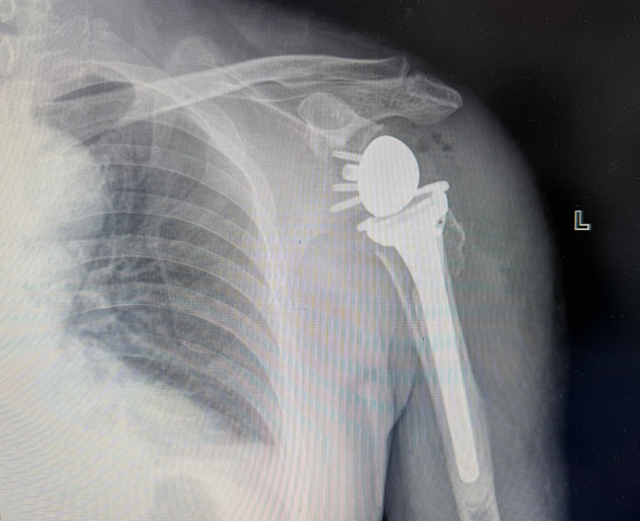

近日,我院骨科团队成功为一名因车祸导致“左侧肱骨近端粉碎性骨折”的老年患者实施高难度 “反式全肩关节置换术” 。术后患者肩关节功能恢复良好,生活质量得到显著提升。

我院骨科团队接诊后,结合影像学资料及详细体格检查,诊断为“左侧肱骨近端粉碎性骨折”,伴有关节结构明显破坏。

针对张大爷的复杂病情,骨科团队经过详细评估后认为,其骨折粉碎严重、肩袖功能丧失,常规固定或半肩关节置换难以取得理想效果,最终决定施行反式全肩关节置换术。

该术式属于国际先进技术,其设计理念与人体正常解剖结构相反——将球形关节面置于肩胛盂侧,盂杯置于肱骨近端。这种“反着装”的设计能够在肩袖功能缺失的情况下,充分发挥三角肌的动力作用,有效完成肩关节的外展、前屈及内旋动作,从而显著降低对肩袖完整性的依赖。

术后第1天,张大爷即在骨科驻科康复治疗师指导下开始被动关节活动;术后3天疼痛明显缓解,可尝试轻度主动锻炼;术后1周复查显示假体位置良好,肩关节稳定性恢复满意。